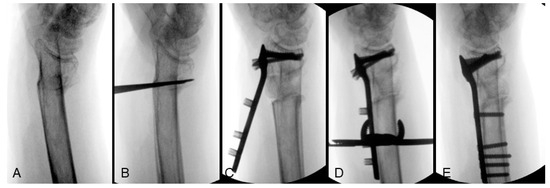

Tilt and Inclination

In cases with a relatively small osteotomy gap, intrafocal Kapandji K-wires are utilized to facilitate adjustments in alignment. One K-wire is placed dorsally to act as a lever for adjusting the volar tilt, while another intrafocal Kapandji K-wire is positioned radially to correct the radial inclination. However, if greater lengthening is required, resulting in a larger osteotomy gap, the lever effect of the Kapandji K-wire may diminish. In such cases, the distal fragment can be initially secured using the corresponding distal locking screws of a volar locking plate, utilizing the plate as a reduction template. By clamping the shaft end of the plate to the radial shaft, substantial correction of the volar tilt can be achieved even at large angles. Figure 2 illustrates the sequential process of tilt correction for an extra-articular distal radius malunion (Figure 2A). The osteotomy plane was initially formed by multiple K-wires (Figure 2B) and a defect was filled with allograft after radial height lengthening. An anatomical plate was used as a reduction template that the volar tilt was corrected by applying the subchondral articular locking screws first (Figure 2C), then clamping the plate to the shaft to rotate the articular fragment into the correct position (Figure 2D), and finally achieving definitive fixation by inserting all the remaining screws (Figure 2E).

Figure 2. Correction of tilt from extra-articular distal radius malunion: (A) preoperative lateral view; (B) osteotomy plane created by multiple K-wires; (C) allograft insertion and apply the articular locking screws of volar locking plate; (D) volar tilt corrected by clamping the plate to the radial shaft; (E) definitive fixation. Image courtesy of the corresponding author Chen-Yuan Yang, MD.